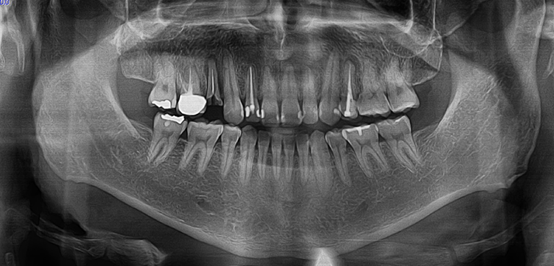

↑這是根管治療完成時的X光